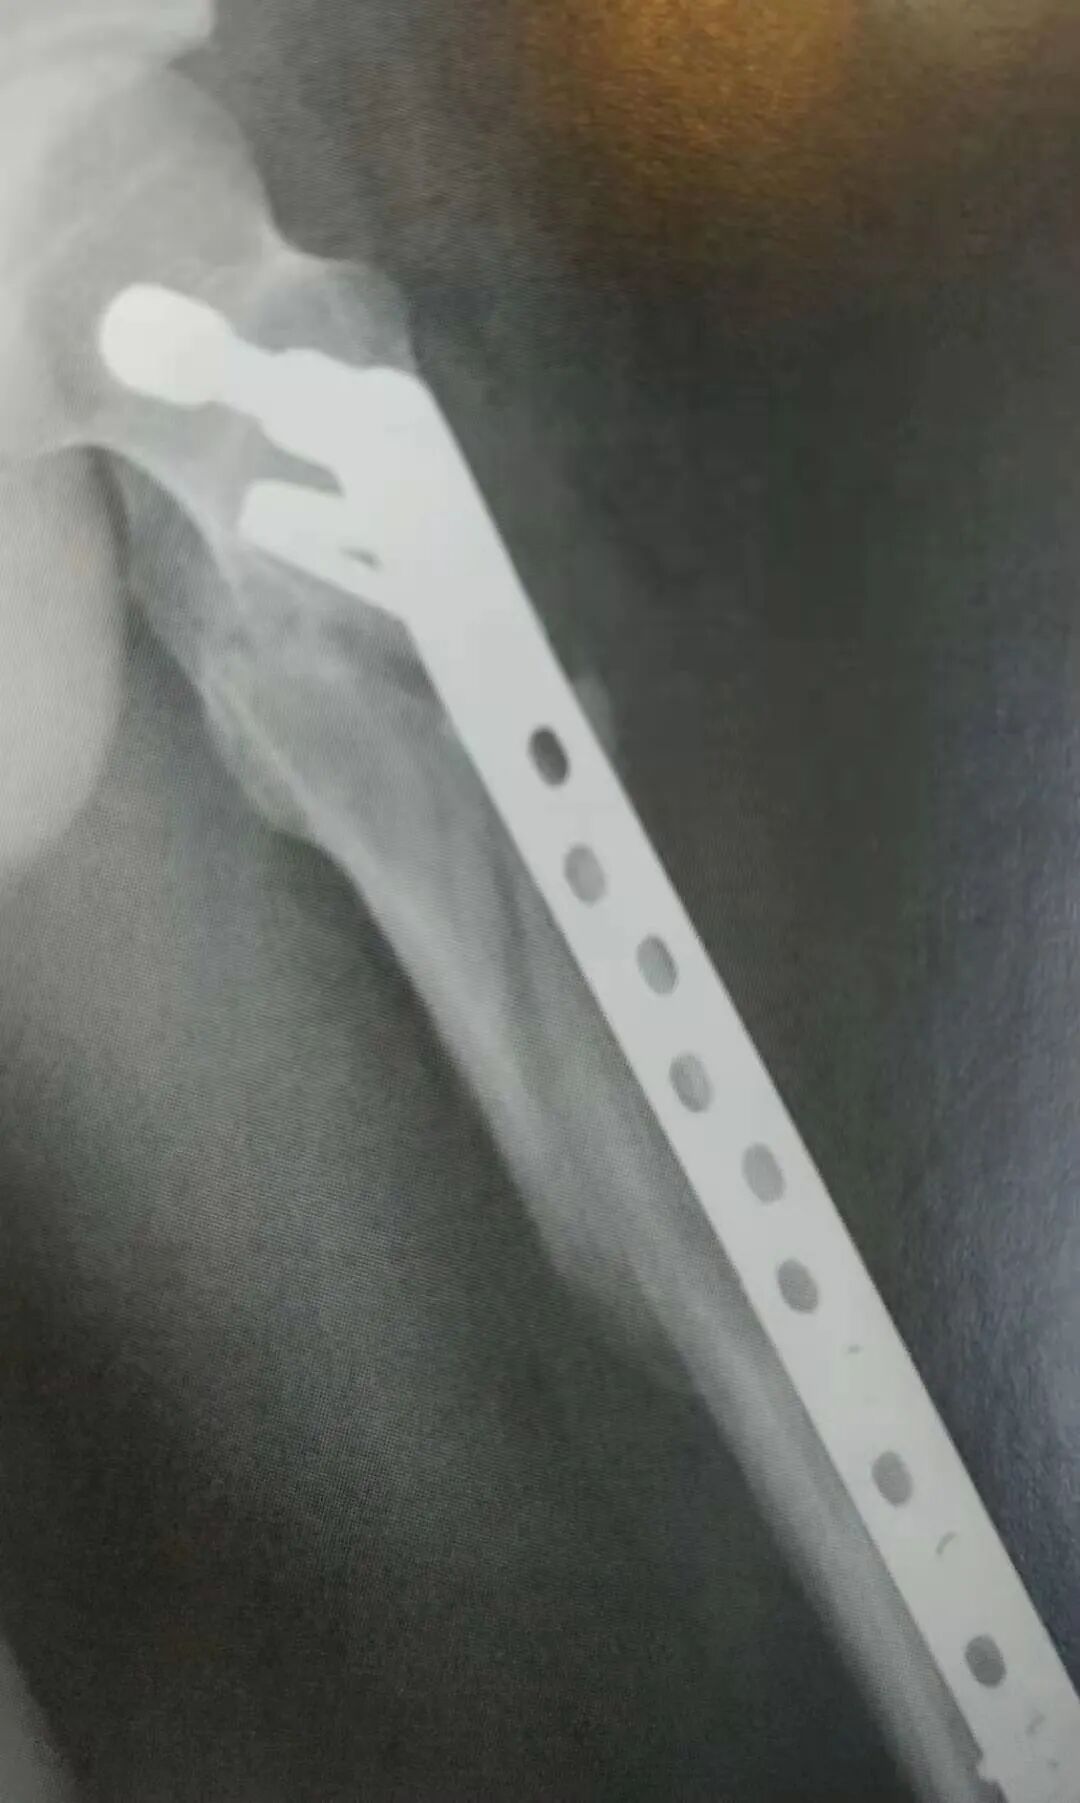

▲ 粉碎性转子下骨折

1)粉碎性转子下骨折

• 通过髓内钉或微创桥接接骨板进行相对稳定固定。